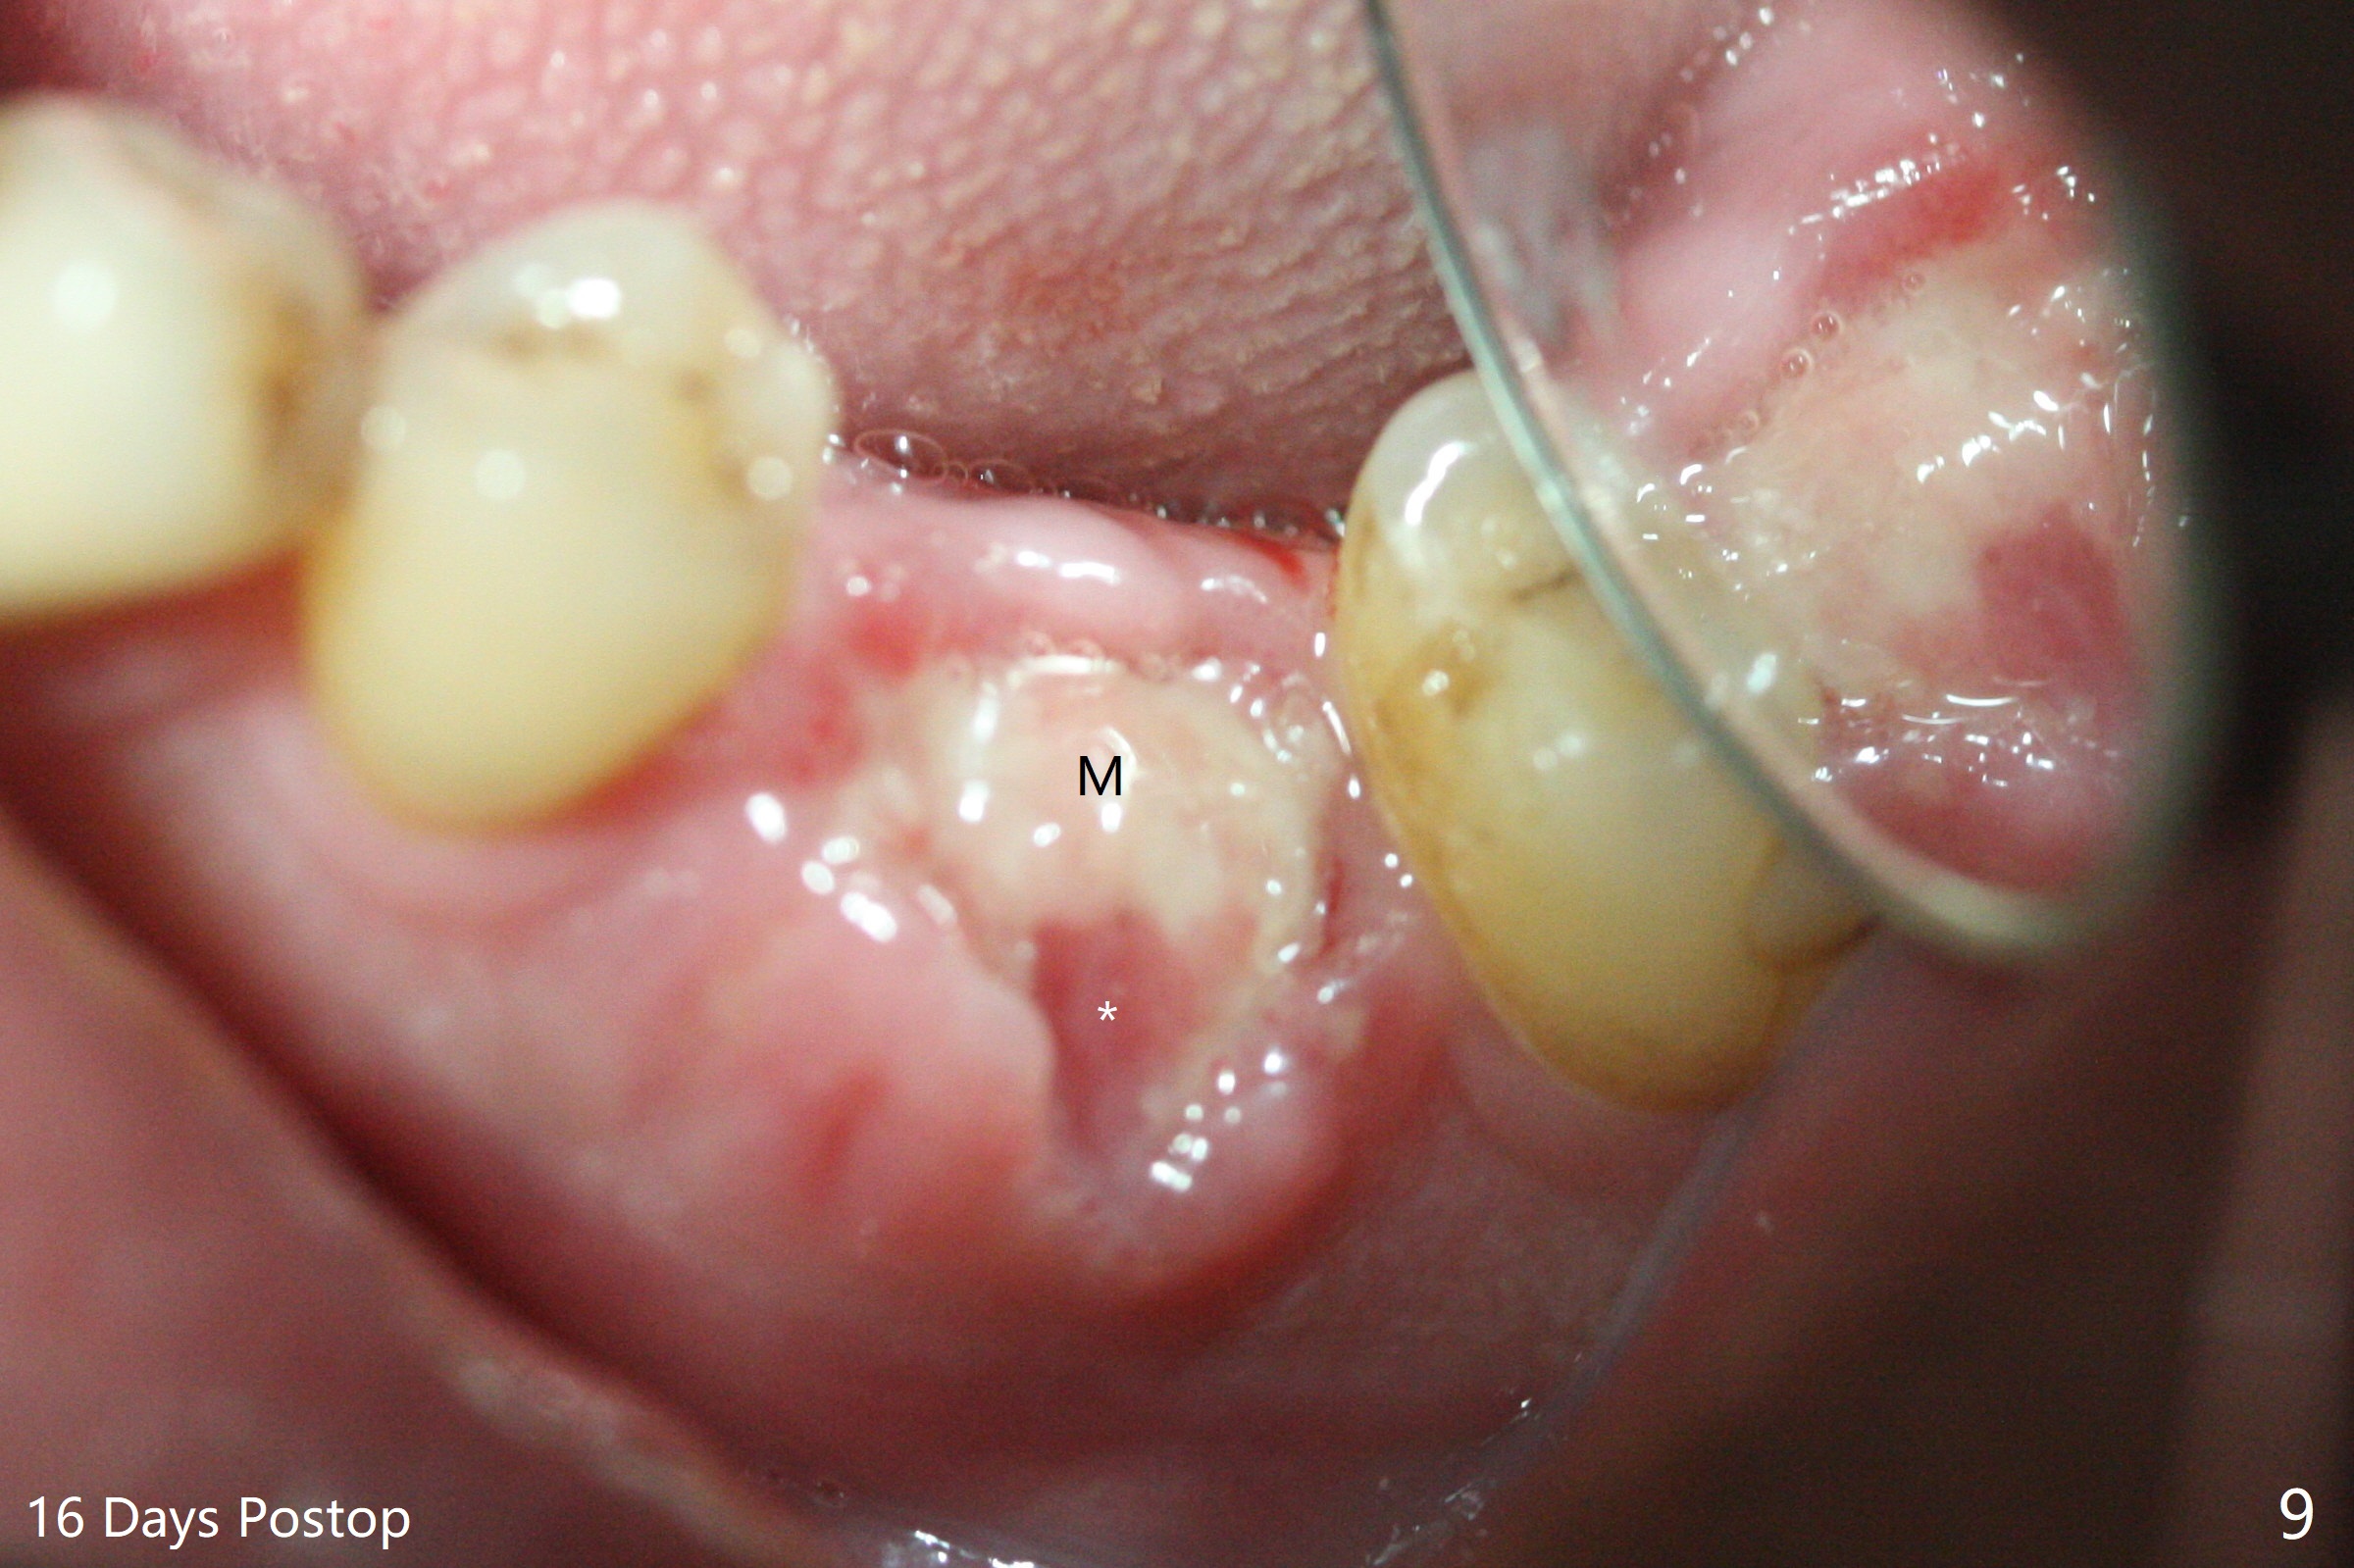

When the patient returns for #15 comp, the bone resorption and swelling at #19 are worse than those 3 years ago (Fig.1,2). After debridement, the mesial socket is large, while the septum is thin, irregular and with undercut (Fig.3). It seems difficult to obtain primary stability for an immediate implant. Vanilla bone and cortical bone hydrated with GEM21 S are placed for socket preservation (Fig.4,5), followed by 12x12 mm BioXclude and 4/0 PGA. In fact the bone height is limited for an immediate implant (Fig.6 (5x10 mm)). There is not enough bone in the septum for primary stability (Fig.7 (cross section of 3D image; L: lingual)). The socket heals 16 days postop (Fig.8). It appears that the granulation tissue is covered by a thin layer of granulation tissue (Fig.9 *), while the membrane remains in place (M). In fact the bone graft remains in the soft tissue zone as well as the hard tissue one (Fig.10). In spite of no apparent loss of bone graft (Fig.4,10), the graft seems to shrink in height 3.5 months postop (Fig.11), while the crest decreases (compare Fig.1 and 11). The keratinized gingiva is wide, but the alveolus reduces in width (Fig.12). The buccal crestal bone is lost 3.5 months postop (Fig.13).